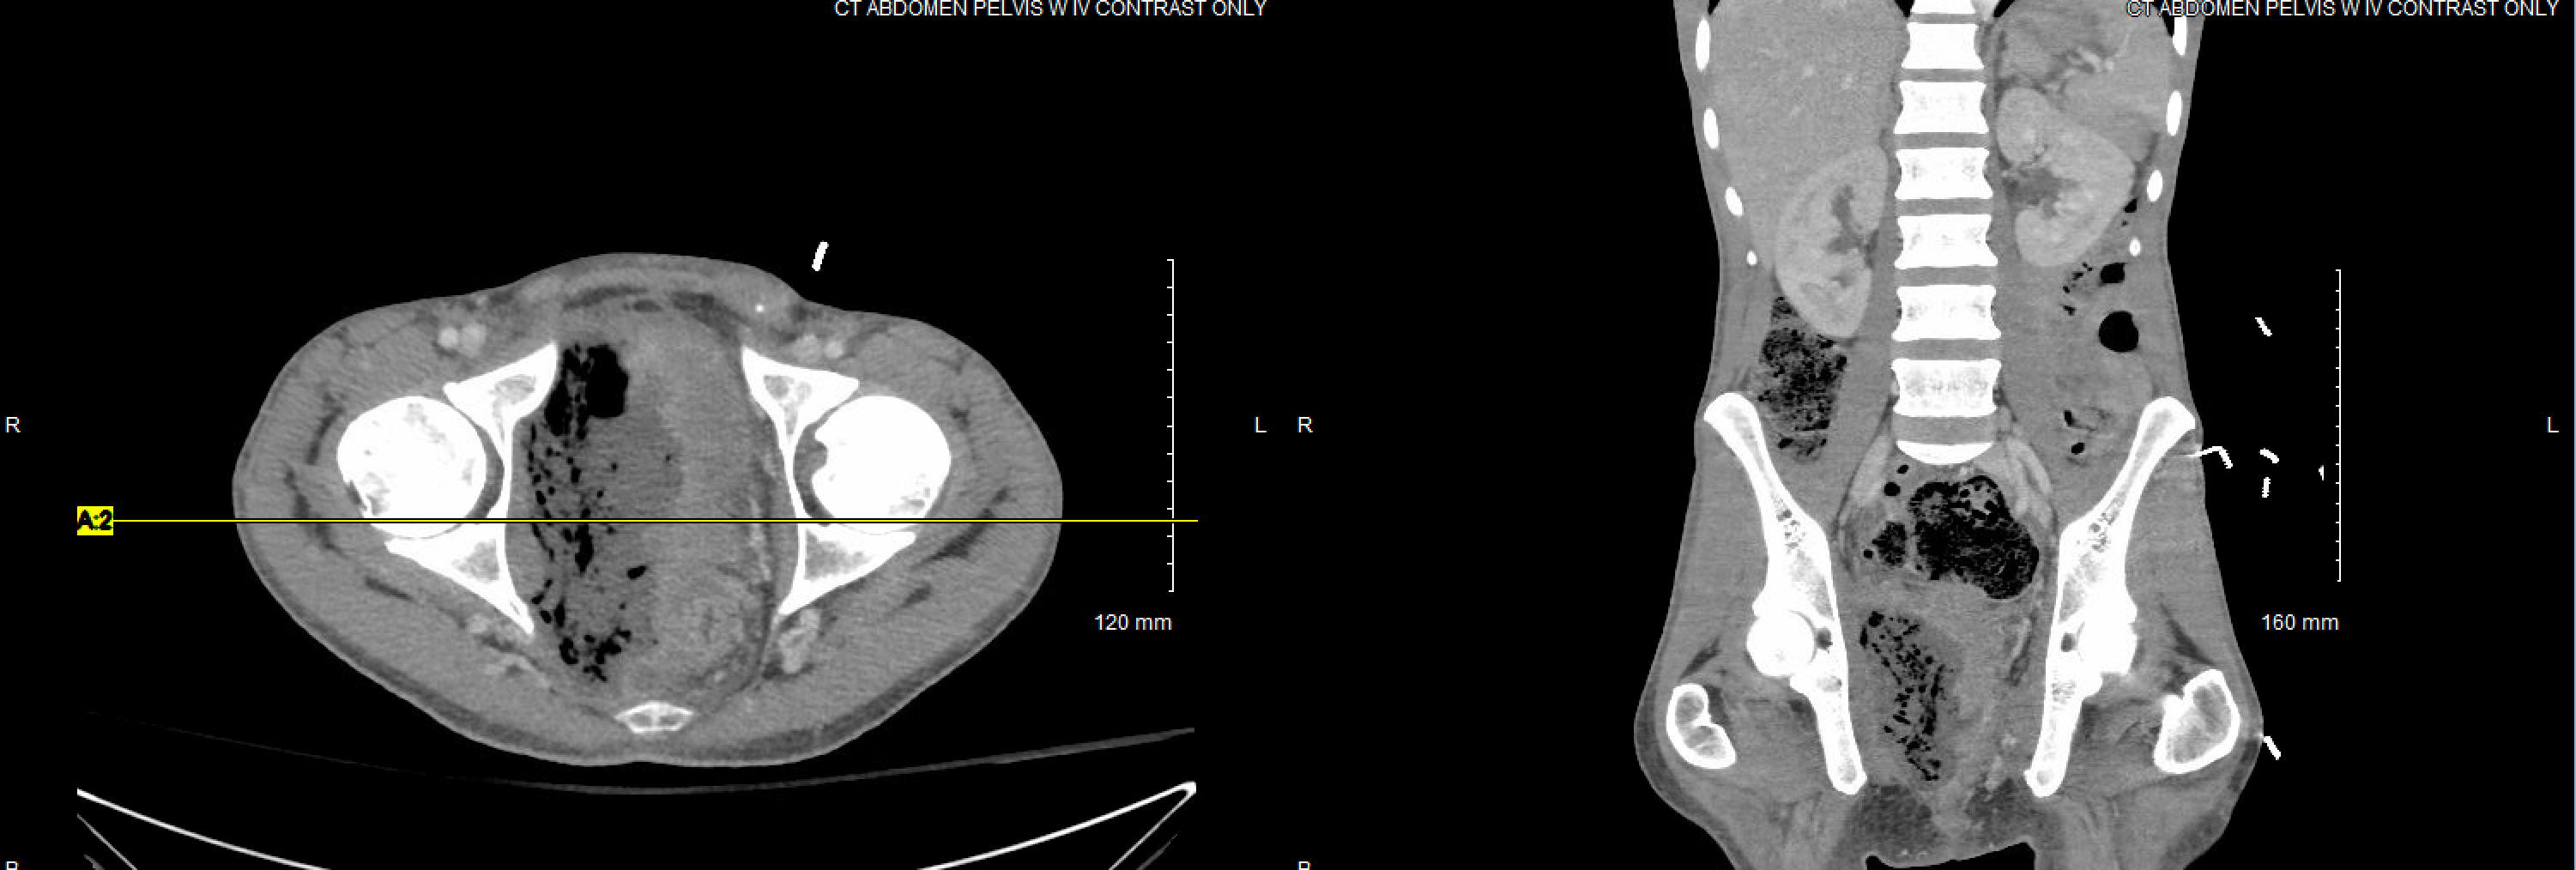

CT scan of the abdomen and pelvis with IV contrast demonstrating a large, gas-filled fluid collection in the deep pelvis, obliterating the normal borders of the rectum and bladder.